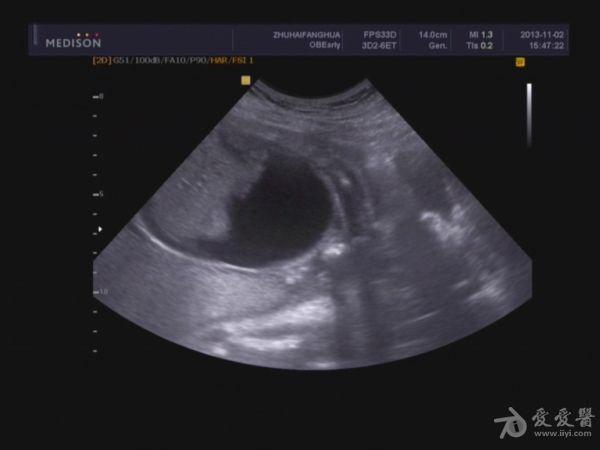

胎儿胸腹腔积液,巨大胎盘。

本帖最后由 jlslst 于 2013-11-2 21:06 编辑 女 25岁,中期孕胎儿产前超声筛查,超声所见:BPD:53mm(22w+1d), H C:212mm(23w+2d),A C:329mm, F L:38mm(23w+0d),HUM:不清,AFD:14mm,AFI:38mm,

单胎妊娠;臀位,颅骨环基本完整,脑中线居中,CER: 24mm,CM:不清,双侧丘脑可见,侧脑室未见明显扩张,小脑可显示欠清,胎儿颈项部欠清,胎儿颜面显示不清,胸腔增大内见积液,腹壁完整,肝、可见,腹腔内大量积液,最大径约:71mm,胸腔内积液最大径:11.4mm,胃及膀胱显示不清。双肾显示不清。双侧四肢长骨显示欠清。

胎盘:附着于子宫后壁,厚度44mm,成熟度:0级,范围面积大,几乎覆着全后壁。

脐带:结构正常,脐动脉血流参数:SPV:33cm/s,PI:1.0,RI:0.62,S/D:2.6。典型图片如下:

诊断意见: 1.宫内中期孕,单胎,胎儿存活,

2.胎儿畸形,胸、腹腔大量积液,

3.超大胎盘,羊水少。